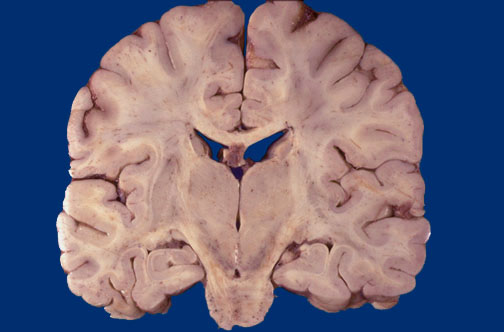

Identify the following regions of the normal brain by clicking in the image below:

Substantia Nigra - Putamen - Tail of Caudate Nucleus